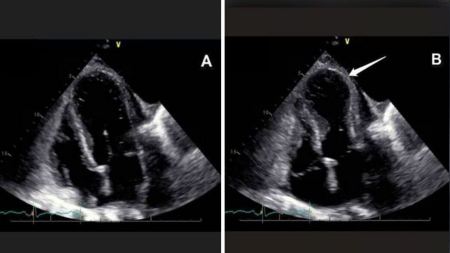

في "زيڤ"، التقت عينات بـ الدكتور صموئيل توبياس، الخبير في جراحة الأعصاب ومدير وحدة جراحة الأعصاب في المركز، الذي شخّص منذ الفحوصات الأولى مدى جدية حالتها الصحية. كان عبارة عن ورم كبير، غني بالأوعية الدموية، وملتصق بأحد الأوردة المركزية المسؤولة عن تصريف الدم من الدماغ، وهي منطقة حساسة للغاية، حيث أن أي خطأ فيها قد يؤدي إلى ضرر عصبي جسيم أو حتى خطر على الحياة.

هذا وقد ُجريت العملية في "زيڤ" بنجاح تام وتم استئصال الورم بالكامل. وفقط بعد ذلك، ظهرت نتيجة فحص الأنسجة (الباثولوجيا) لتكشف عن مفاجأة مذهلة تشير الى ان الورم هو ورم سرطاني نادر يُسمى بورم الخلايا الحوطية (Solitary Fibrous Tumor / Hemangiopericytoma)، وهو ورم خبيث نادر جداً من الدرجة الثالثة، يمثل أقل من 1% من إجمالي أورام الدماغ، ويُعد نادراً حتى بالمقاييس العالمية. لاحقاً، خضعت عينات لعلاج إشعاعي مكمّل، وهي اليوم تحت المتابعة دون أي دليل على عودة المرض، حيث عادت لممارسة حياتها وعملها بشكل كامل.

بدوره تطرق الدكتور صموئيل طوبايس الى حالة عينات الطبية وقال:"نحن نتحدث عن حالة معقدة للغاية. كان الورم ملتصقاً بأماكن حيوية وحساسة في الدماغ، وفي المرحلة الأولى بدا وكأنه ورم حميد. كانت نتيجة فحص الأنسجة (الباثولوجيا) مفاجأة كبيرة؛ فهذا ورم نادر جداً، لدرجة أن جراح الأعصاب قد لا يصادف سوى حالات معدودة منه طوال حياته المهنية. لقد نجحنا في استئصال الورم بالكامل، ولاحقاً تطلب الأمر علاجاً إشعاعياً. حالياً، تخضع عينات للمتابعة دون أي دليل على عودة المرض، ومن المُثير جداً رؤيتها تعود لممارسة حياتها الطبيعية".